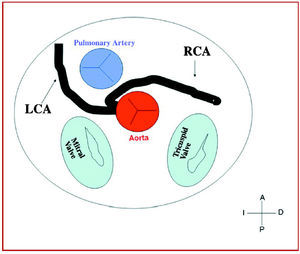

3. Preaortic or interarterial (between the aorta and the pulmonary artery), in which the anomalous right coronary, left anterior descending or left main coronary artery cross the septum or the aortopulmonary space. This is the course that has most frequently been related to signs of ischemia and/or sudden death (Figures 7 and 8).

Figure 7. Diagram showing the interarterial course of a right coronary artery (RCA) originating in controlateral sinus.